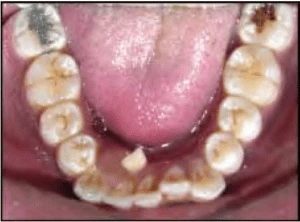

Các răng sau bị xoay chiếm nhiều khoảng hơn. Xoay lại các răng sau có thể giúp lấy lại khoảng. Khoảng trống được lấy lại khác nhau tùy thuộc vào răng liên quan và mức độ xoay. Với một góc xoay như nhau, răng cối lớn chiếm nhiều khoảng hơn so với răng cối nhỏ; trong khi răng trước chiếm ít khoảng hơn.

Hình 6A. Răng sau xoay chiếm nhiều khoảng trống hơn